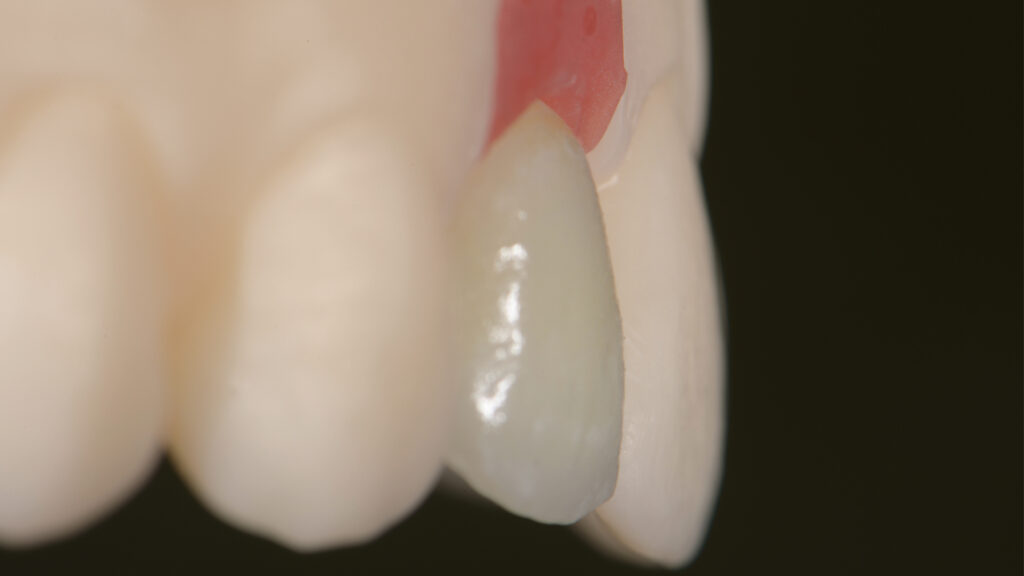

Vita Ambria (Vita Zahnfabrik, Bad Säckingen) ist ein mit Zirkonoxid verstärktes Lithiumdisilikat mit hoher Festigkeit (>500 Mpa), das in der Presstechnik verarbeitet wird. Die Keramik eignet sich besonders für die effiziente Herstellung von hochästhetischen, langlebigen Restaurationen wie Overlays und Teilkronen. Das Presskeramik-System enthält Presspellets in den Transluzenzstufen T (transluzent) und HT (hochtransluzent) (Abb. 15). Ein Vorteil ist, dass die aus Vita Ambria gepresste Restauration vollanatomisch und monolithisch bemalt und glasiert oder mit der Verblendkeramik Vita Lumex AC (Vita Zahnfabrik) fertiggestellt werden kann. Nach dem Modellieren des hauchdünnen Käppchens (Abb. 16) und dem Pressen erfolgt das Ausbetten der Keramikschale. Die minimale Reaktionsschicht kann mit geringem Druck (2 bar) abgestrahlt werden, so dass passgenaue Ergebnisse effizient erzielt werden. Da die Schale in der Farbe A1 (HT-Rohling) gepresst wurde (Abb. 17) und die Schichtstärke nur 0,2 bis 0,3 mm beträgt, wirkt sie sehr transluzent (Abb. 18). Es folgt die Verblendung mit Vita Lumex AC. Hier zeigt sich ein weiterer Vorteil für die Umsetzung dieses Falles. Denn die Verblendkeramik kann auch auf Zirkonoxidgerüsten verwendet werden. Vita Lumex AC ist eine leutzitverstärkte Glaskeramik zur Verblendung vollkeramischer Gerüste aus Zirkondioxid-, Lithiumdisilikat- und Feldspatkeramik sowie zur Herstellung von keramischen Veneers.

Individuelle Minimal-Schichtung

Vor dem Brand wird etwas „Smoky White“ auf das Käppchen gestreut, um den Helligkeitswert zu erhöhen (Abb. 19). Eine Aufnahme unter UV-Licht verdeutlicht die Fluoreszenz der gestreuten Keramikmasse (Abb. 20). Die Vorteile der Streutechnik sind keine Erfindung von uns. Vielmehr hat uns unser Kollege und Freund Oliver Brix darauf hingewiesen, wie solche Käppchen vorbehandelt werden können, um eine bessere Tiefenwirkung zu erzielen. Für den ersten Hauptbrand wird interdental/zervikal eine dünne Schicht Effekt-Chroma aufgetragen und die anatomische Form mit etwas Dentin A1 ergänzt. Nach einem Cutback (Abb. 21) des inzisalen Drittels wird eine Mischung aus Schneidemasse sowie „Light“- und „Waterdrop“-Masse (tranzluzente blau/graue Masse) im Verhältnis 1:1 als Schneideteller aufgebaut (Abb. 22). Auf Opakdentin wurde aus Platzgründen und zur besseren Sichtbarkeit der natürlichen Zahnfarbe verzichtet. Die dünne Kappe bietet genügend Transluzenz und Helligkeit, um mit einer dünnen Schicht Verblendkeramik die gewünschte Helligkeit, Sättigung und Farbe zu erzielen. Die Individualisierung der Inzisalkante erfolgt mit der wärmeren und fluoreszierenden Keramik „Saffron“, die mit Interno Liquid angemischt wird (Abb. 23). Vorteil dieser Mischung ist, dass das Liquid die Masse besser einfärbt und so die Sättigung mit bloßem Auge kontrolliert werden kann. Außerdem ist die angemischte Masse sehr plastisch und lässt sich kontrolliert auf den Inzisalteller auftragen. Zur Imitation von weißlichen Kalkflecken wird „Smoky White“ mit Interno Liquid angemischt und mit dem Pinsel in die Schneidemasse eingearbeitet (Abb. 24). Nach dem ersten Brand der minimalen Schichtung sind alle Merkmale gut sichtbar. Wie in der Natur kommen sie aus der Tiefe (Abb. 25 bis 27).

Beim zweiten Brand wird die minimale Schichtung mit „Tranzluzent Clear“ ergänzt, um eine Art Filtereffekt zu erzeugen. Dies simuliert einen 3D-Effekt (Envelope-Technik), der feine Details aus der Tiefe erscheinen lässt. Der distale Kontaktpunkt wird mit etwas Dentin aufgebaut (Abb. 28). Das Gerüst wurde aus einem HT-Rohling gepresst, um einen Chamäleoneffekt zu erzielen. Dies ist mit transparenten Massen gut möglich. Dieses Vorgehen sollte jedoch nur dann gewählt werden, wenn keine Farbveränderungen (z. B. bei verfärbten Zähnen) gewünscht sind. Grundsätzlich erspart ein detaillierter Auftrag der Keramikmassen ein aufwendiges Beschleifen der Keramikrestauration im Nachhinein (Abb. 29).

Nach dem zweiten Brand wird die Form kontrolliert, um dann auf dem ungesägten Modell die Kontaktflächen und die Ausbildung der Leisten zu überprüfen (Abb. 30 und 31). Die labialen und distalen Leisten definieren die Dimension und die Grundform des Zahnes (Abb. 32). Abschließend wird das Veneer fertiggestellt; es erfolgt ein Glanzbrand (Abb. 33). Die Feinabstimmung des Glanzgrades bei Einzelkronen ist ebenso wichtig wie alle anderen Parameter (z. B. Helligkeit, Sättigung, Farbe). Um einen matten Glanz zu erzielen, wird in diesem Fall eine kürzere Haltezeit von 30 Sekunden und eine niedrigere Endtemperatur von 745°C gewählt. Ein zu hoher Glanzgrad würde den künstlichen Zahn „verraten“. Die Oberflächenstruktur ist patientenspezifisch. In die Zahnoberfläche werden Perkymatien – feine horizontale Wachstumsrillen – eingearbeitet, die mit den Jahresringen eines Baumes vergleichbar sind. Es ist wichtig, die Oberflächentextur dem Restgebiss anzupassen. Auf der Oberfläche entstehen durch die Lichtstreuung der Mikrostruktur bestimmte Lichtreflexe (Abb. 34). Die Natur macht es vor: Durch die Beschichtung der keramischen Restauration mit Goldpulver werden die natürlichen Makro- und Mikrostrukturen deutlich sichtbar (Abb. 35). Zudem macht eine „polar_eyes“-Aufnahme (Kreuzpolfilter) die keramische Schichtung im Zahninneren sichtbar (Abb. 36). Die Aufnahme zeigt die natürliche Fluoreszenz und insbesondere die mit „Smoky White” erzielte Imitation der Kalkflecken (Abb. 37). Dem Einsetzen des Keramikveneers 22 schließt sich die implantologische Therapie regio 12 an.